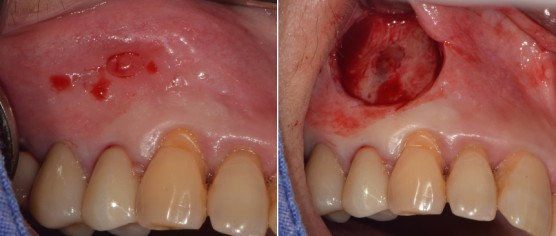

뼈 이식으로 마무리 함.

이미지

마무리 후 x-ray 촬영